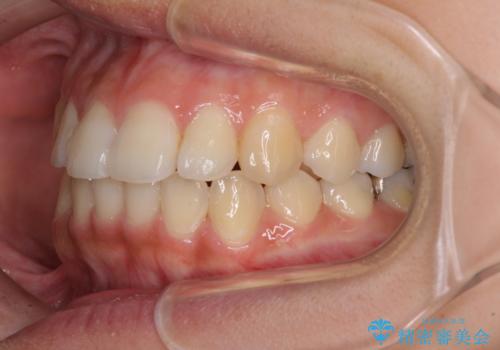

前歯の突出感とデコボコ インビザラインで改善

- 上下前歯のデコボコを気にして来院された患者様です。

インビザラインによる上下歯列の側方拡大と後方移動、IPR(歯と歯の間を削る)にるスペースの獲得により歯列を整えることとしました。

右上の小臼歯は歯根癒着をしており、様々な方法を試みるも動かすことができませんでした。

それでも奥歯のかみ合わせに不自由はなく、歯列をきれいに整えることができました。